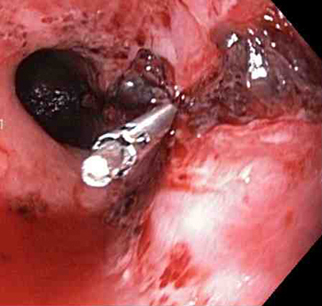

Laceração de Mallory-Weiss

Um clipe do tipo "through-the-scope" instalado no centro da lesão (sem infusão prévia de adrenalina, neste caso)

Do acervo de Juan Carlos Munoz, MD, University of Florida